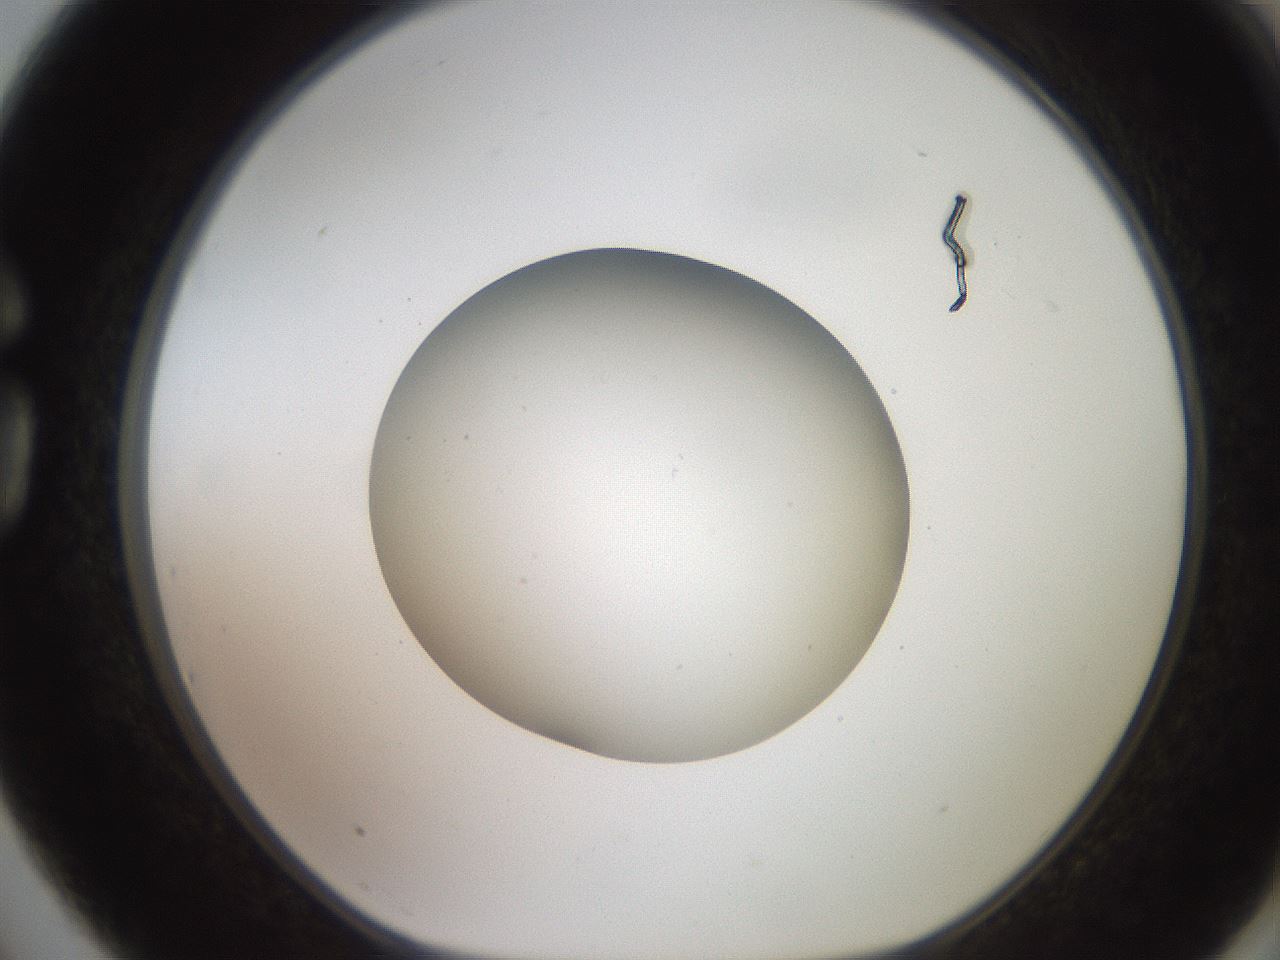

folderID619_plateID1619_batchID6747_wellNum75_profileID1_d1_r107916_ef.jpg